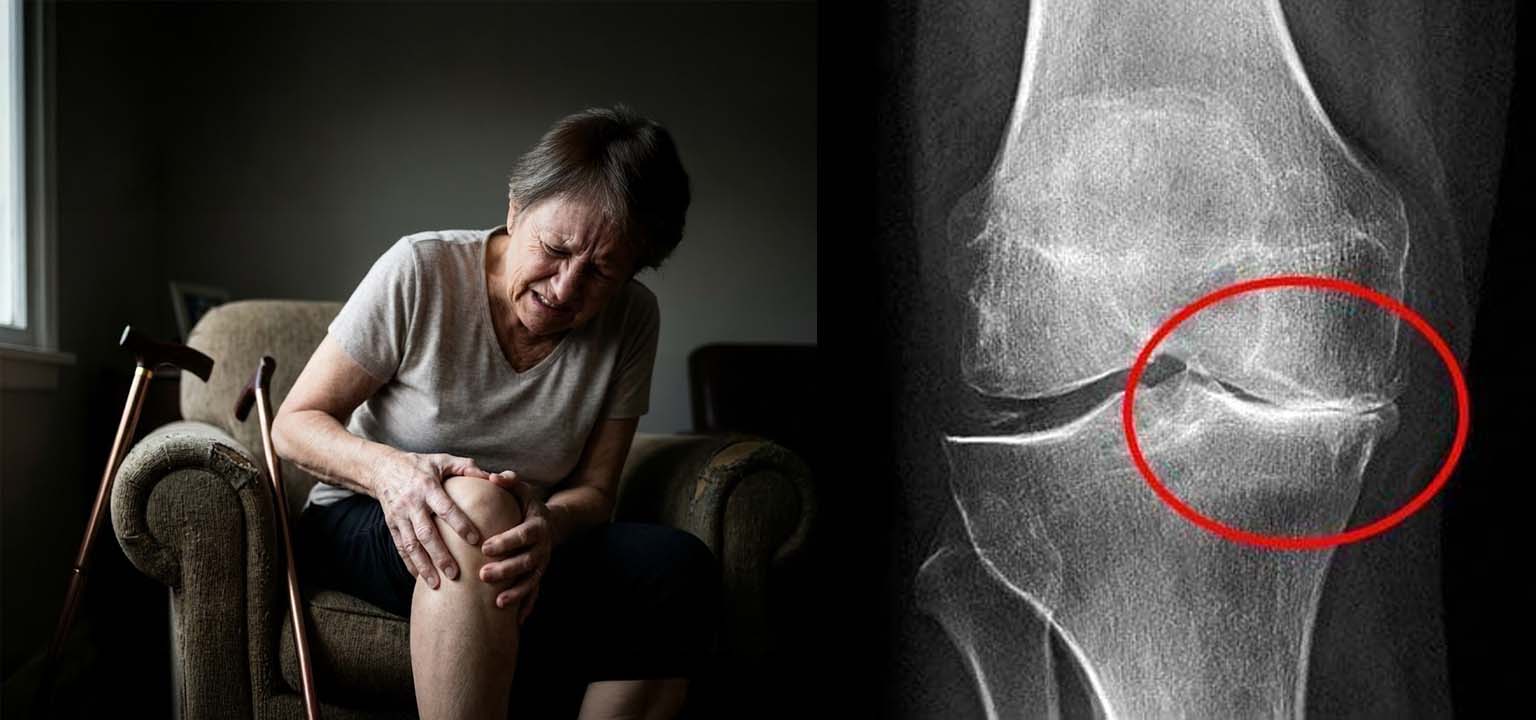

Mi chiamo Anna. Solo 3 mesi fa, ero seduta nello studio del Dottor Rossi. Lui guardava le mie radiografie e scuoteva la testa senza pietà: "Anna, la tua cartilagine è marcia. È osso contro osso. Senza l'operazione, sarai un peso morto per i tuoi figli entro Natale."

FIG 1. La mia radiografia mostrava un danno che i medici definivano "irreversibile".